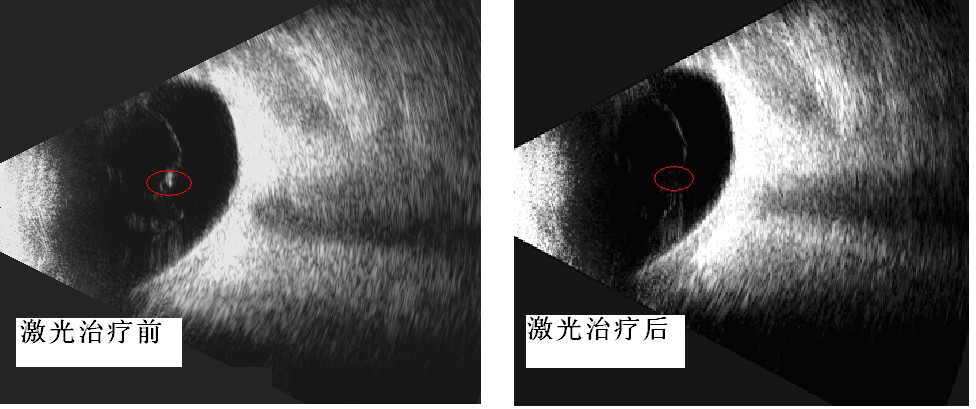

近日成人导航已为首批飞蚊症患者进行治疗,这些患者倍受飞蚊症折磨,通过2-3次玻璃体激光消融治疗,取得了满意的疗效。从眼部B超检查也显示激光治疗前后玻璃体混浊也有了明显的改善。